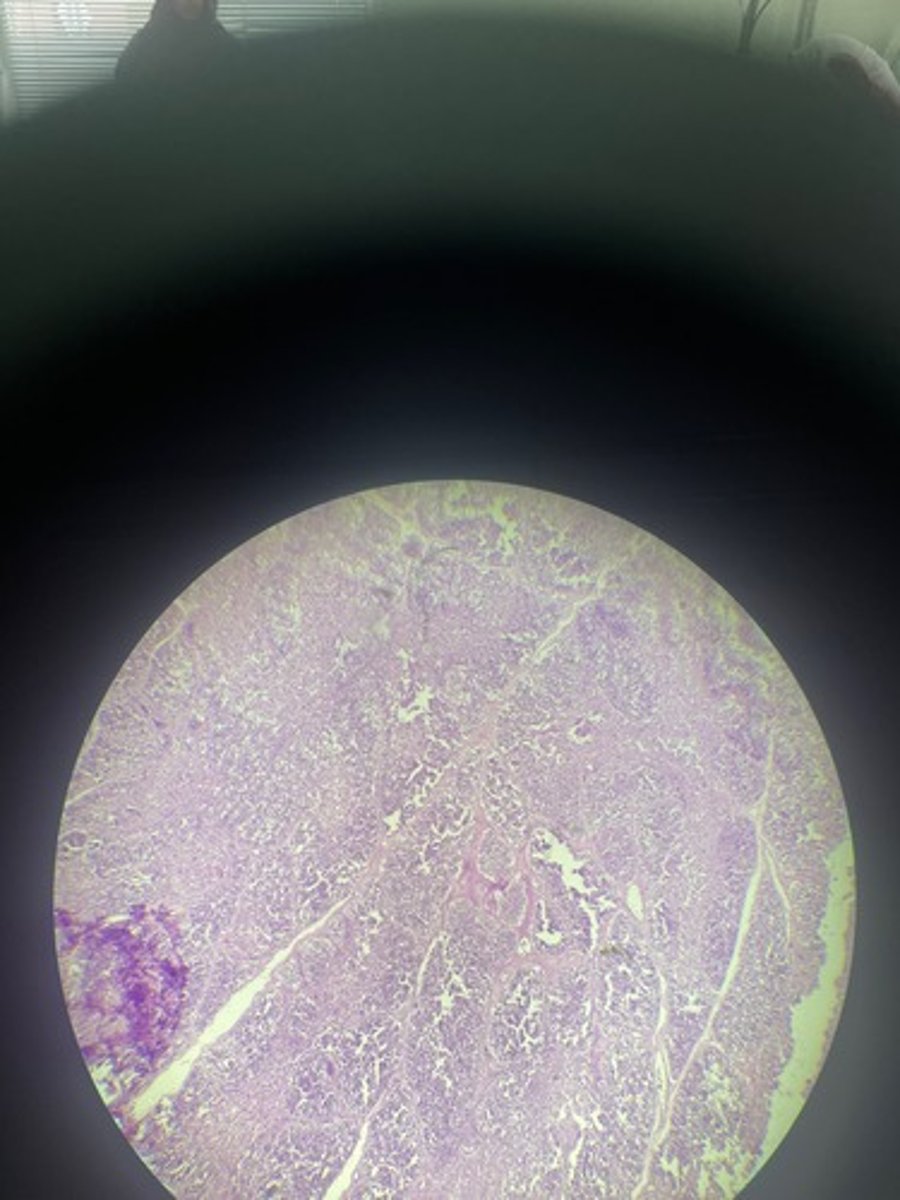

Thymus HE

Thymus HE

Thymus HE

Thymus HE

Thymus HE

Thymus HE

Thymus HE

Thymus HE